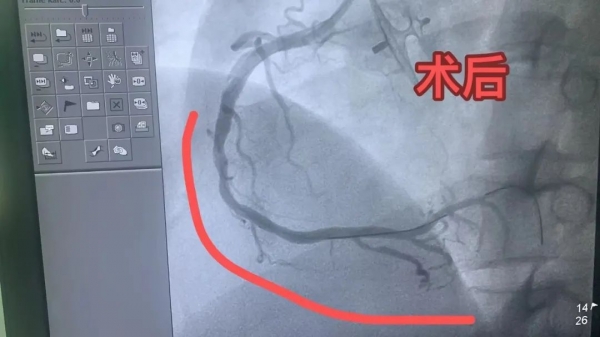

急診行心電圖示:下壁ST段抬高,診斷為急性下壁ST段抬高型心肌梗死。立即啟動胸痛中心綠色通道,給予救治。田豐主任帶領(lǐng)的團隊緊急在局麻下行冠狀動脈造影術(shù)+經(jīng)皮冠狀動脈球囊擴張成形術(shù),手術(shù)順利完成。